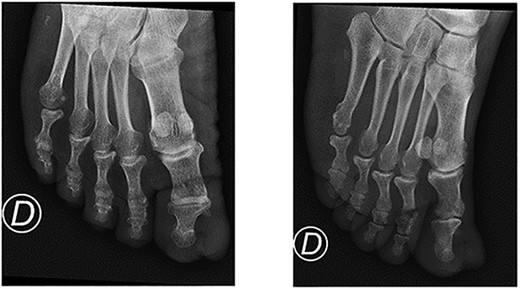

A 64-year-old sub-Saharan African male with diabetes with a long-standing history of a recurring slow-growing periungual mass of the left great toe after multiple surgical wedge excisions for an ingrown toenail presented to the emergency department with acute pain, bleeding and local swelling of the lesion. Physical examination revealed a painful periungual mass (Fig. 1). The toe’s range of motion was conserved and there was no sign of ischemia. An X-ray was performed and did not reveal any bone erosion or osteolytic lesions (Fig. 2). Neither computer tomography (CT) scanning nor magnetic resonance imaging (MRI) were performed. The emergency doctor initially treated the lesion with silver nitrate treatment, and the patient was referred for an orthopaedic consultation for treatment of a recurrent ingrown toenail.

Bone involvement (bone erosion or osteolytic lesions) can be present in one-third of cases [7]. In our case, standard X-ray did not reveal any bone involvement. We did not perform a CT scan or MRI before surgical resection since it would have led to a delayed diagnosis and extra cost. Nevertheless, in unclear cases, MRIs can prove useful. Moreover, a CT scan can detect soft-tissue calcifications and bone erosions [9]. High-resolution ultrasonography (US) with Doppler is readily accessible and cost-effective and can detect small benign tumours and tumour-like conditions of the nail apparatus. However, the quality of the US examination remains operator dependent [9].